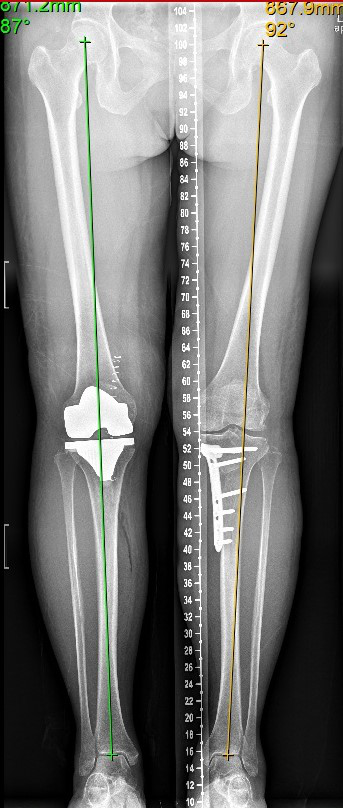

—胫骨高位截骨术(high tibial osteotomy, HTO),是通过胫骨近端微创楔形开槽,改变下肢力线的异常分布,降低内侧间室的压强,将其恢复到软骨能够承受的正常范围,使得受损的膝关节内侧不负重或者少负重,可明显缓解疼痛和改善步态,改善膝关节生物力学环境和有效血液循环,促进内侧间室关节软骨修复,减轻膝关节疼痛,恢复膝关节正常活动。从而避免换关节,或者推迟换关节的时间。特别适合相对年轻活跃、MPTA(胫骨近端内侧角)小于85度或大于90度的内侧骨关节炎患者。临床实践证明,约三分之二的患者并不需要膝关节置换,可以采用保膝手术治疗,有效率甚至超过全膝关节置

选择的优势:由于属于微创手术,创伤小,出血少,对软组织破坏少,所以患者术后锻炼的时间早,并发症少,恢复越快。

术后当天床上活动,术后第2天就开始患肢部分负重,4周开始逐渐增加负重,6-8周后可以完全负重。由于此微创手术不破坏关节内的任何重要结构,包括软骨、交叉韧带、半月板,因此被称为为真正的保膝手术,它可以完整的保留膝关节的功能和本体感觉。手术只相当于一次小腿的不全骨折的愈合,所以术后很少发生关节活动受限的情况,患者不需要很辛苦的进行关节屈伸锻炼,就可以达到关节活动自如。充分体现了“保膝”理念,保留了关节的自然运动功能与舒适性,延长患者膝关节的自然寿命。